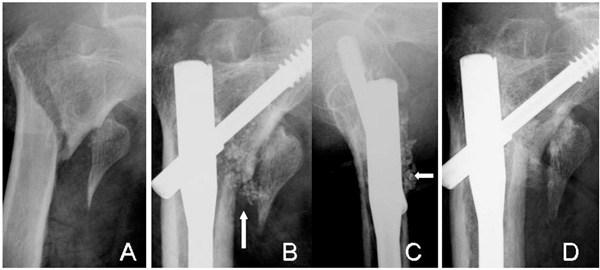

Radiographs of an 83-year-old woman (Case 6) with a displaced lesser trochanter (A). The β-TCP granules are still visible at 4 weeks (arrows) in AP (B) and lateral views (C). The complex is resorbed and bone union of the intertrochanteric fracture has occurred at 12 weeks (D). However, no bridging bone formation is seen between the lesser trochanter and the shaft.

Axial CT images of Case 6. The injectable complex (arrows) has not been replaced by bone at 3 weeks (A). At 8 weeks (B), the complex is partially replaced and is completely replaced by bone at 12 weeks (C). However, it did not reach to the displaced lesser trochanter.